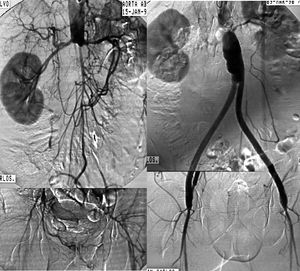

Cirugía de revascularización. La afectación difusa, extensa se trata de forma óptima habitualmente mediante el implante de una prótesis aórtica unifemoral o bifemoral (figs. 5 y 6). Se trata de una técnica de efectos conocidos, bien sistematizada y que ofrece unos resultados en términos de permeabilidad superiores al 85 y el 80% al cabo de 5 y 10 años, con cifras de mortalidad operatoria inferiores al 5%4. Sin embargo, es una cirugía arterial mayor y precisa cuantificar el riesgo quirúrgico para seleccionar a los candidatos más adecuados. En aquellos pacientes de alto riesgo o con un abdomen hostil (múltiples reintervenciones, radioterapia previa, infección activa, etc.) la intervención se realiza mediante las técnicas denominadas «extraanatómicas», que permiten la revascularización de las extremidades por trayectos no anatómicos, y con una menor agresión. Los más utilizados son la cirugía de derivación axilounifemoral o bifemoral, y la femoro-femoral. Ambos tipos de cirugías de derivación se tunelizan por vía subcutánea, la primera por la región lateral del tórax y el abdomen, y la segunda por la región suprapúbica. Pueden realizarse con anestesia locorregional. Las cifras de permeabilidad de las cirugías de derivación extraanatómicas son inferiores, con oscilaciones entre el 40 y el 70% a los 5 años, según la indicación clínica4. Por esta razón, raras veces se indican en ausencia de isquemia crítica.

Fig. 5. Arteriografía que muestra una oclusión aortoiliaca extensa y el resultado tras la realización de una cirugía de derivación aortobifemoral.

Angioplastia/endoprótesis. La angioplastia proporciona sus mejores resultados en lesiones cortas, preferentemente estenosis y no calcificadas en la arteria iliaca común. En estas situaciones, sus resultados a largo plazo son buenos, con cifras de permeabilidad del 70% a 5 años para los pacientes con claudicación41. Sin embargo, cuando se realizan en lesiones más largas, y en especial cuando se recanalizan oclusiones completas, la permeabilidad es claramente inferior. Las ventajas derivadas del implante de una endoprótesis primaria en las angioplastias iliacas han sido evaluadas en ensayos clínicos, con cifras de permeabilidad sólo ligeramente superiores para la endoprótesis sitemática frente a la angioplastia simple42-44. Es probable que la mejor actitud sea implantar una endoprótesis de forma selectiva en los pacientes en los que la angioplastia muestre un resultado inicial subóptimo (fig. 7).

Fig. 7. Imagen arteriográfica de una oclusión de la arteria iliaca primitiva y estenosis de iliaca externa, solucionadas mediante la implantación de una endoprótesis recubierta.